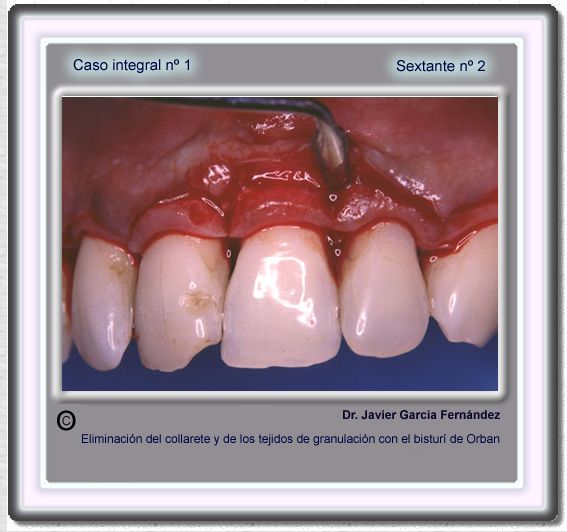

image 34